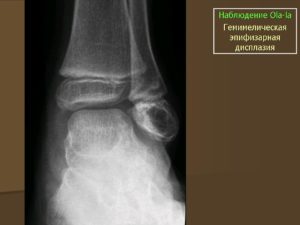

- Тип 2. Множественная дисплазия тазобедренных суставов. Клинические симптомы начинают обнаруживаться по достижении ребёнком возраста 2,5 лет. Он начинает предъявлять жалобы на боли в коленях и голеностопных суставах. Коленные суставы могут быть увеличены в размерах и деформированы. Эпифизы практически всех суставов уменьшаются в размерах и выглядят сглаженными.

- Тип 3. Самые первые симптомы этого типа дисплазии тазобедренного сустава начинают проявляться при достижении ребёнком пубертатного возраста. Походка у него становится «утиной» или «вперевалку». В коленных суставах развивается ограничение подвижности, начинают беспокоить боли. Ребёнок отличается низким ростом и короткими руками. Эпифизы бёдер сглажены, коленные суставы деформируются и увеличиваются в размерах. С течением времени развиваются признаки остеоартроза суставов.